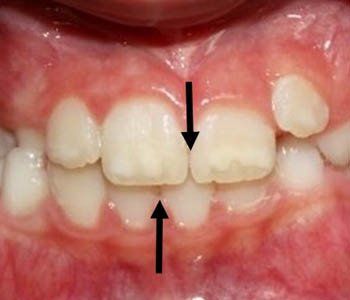

Posterior Crossbite

In the back of the mouth, one or more of the top teeth is stuck inside the bottom teeth.